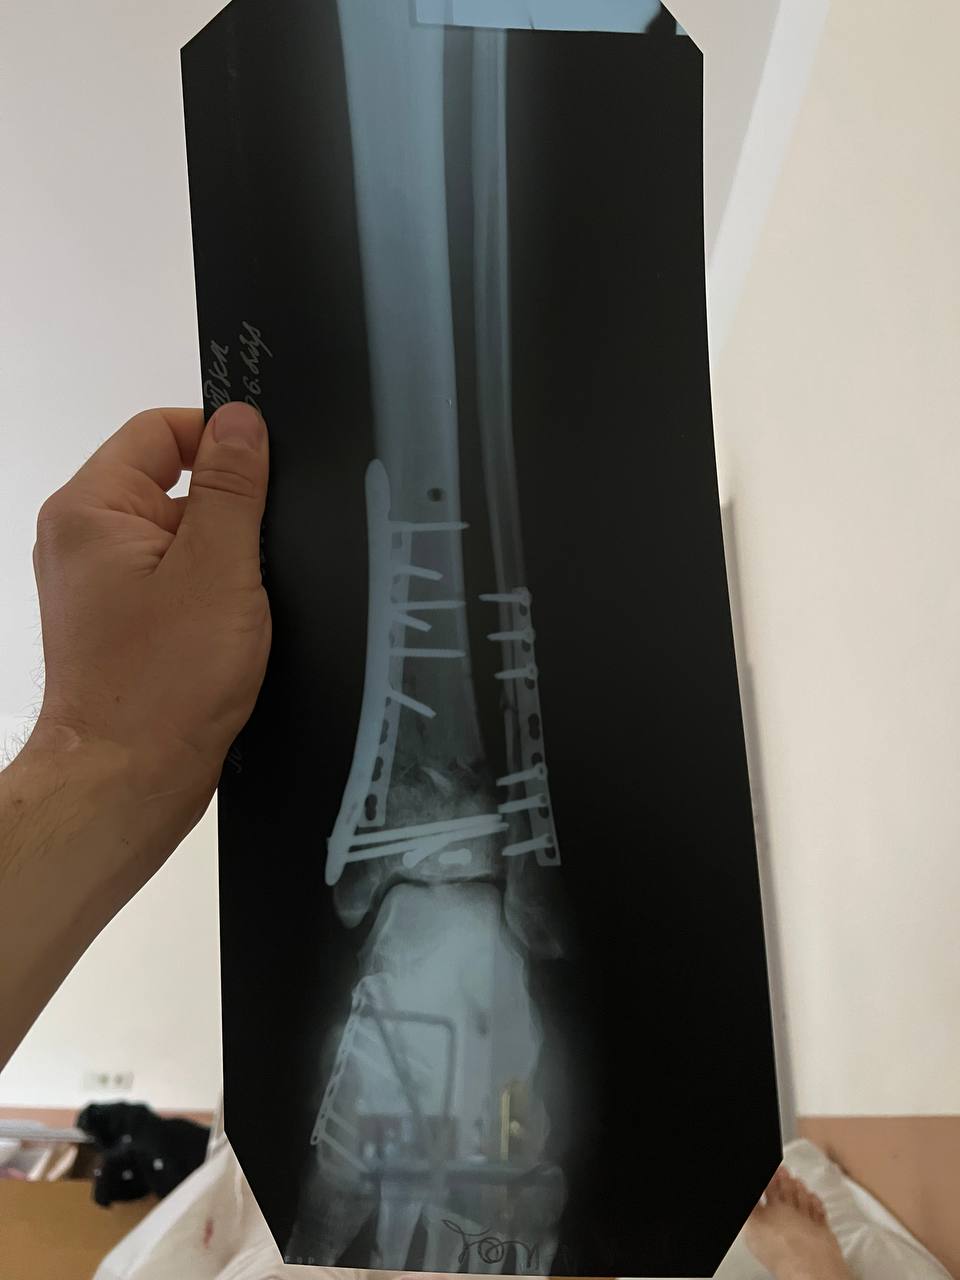

Ruslan had a closed fracture of his left leg, the limb was broken below the knee to the tips of the toes. He underwent four surgeries in more than a year, and now, instead of a joint, there are three large screws. Also, after the injury, he had to stitch up the jaw on both sides.